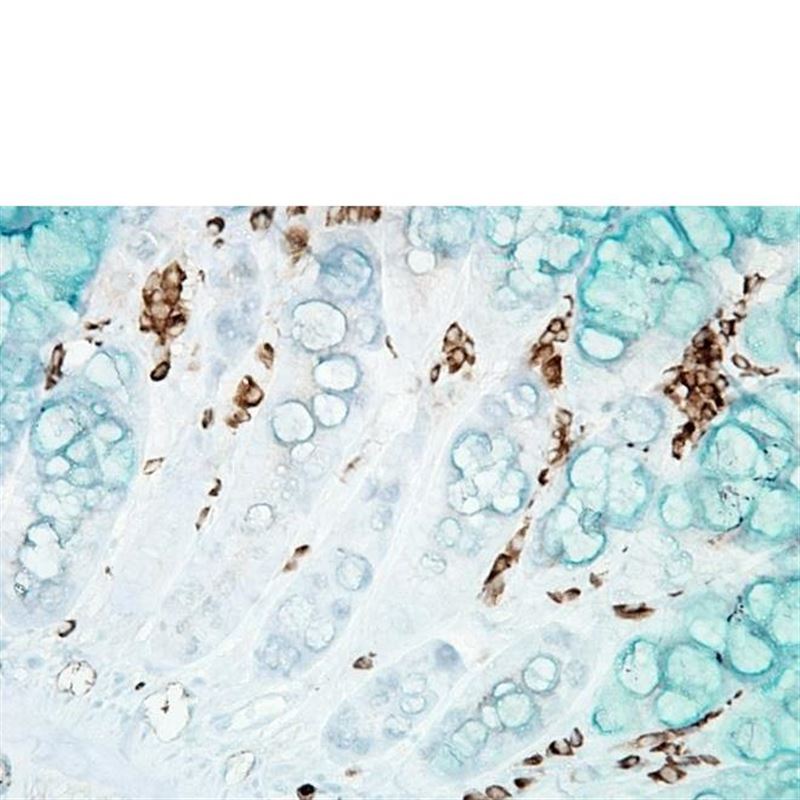

产品名称:Anti-DNA/RNA Damage Antibody 15A3抗体

Anti-DNA/RNA Damage Antibody 15A3抗体

产品名称 | DNA/RNA 损伤(8-OH-dG)抗体 |

产品描述 | 小鼠抗DNA/RNA 损伤(8-OH-dG)单克隆IgG2b |

适用物种 | 与物种无关 |

应用范围 | IHC, ICC/IF, ELISA, DB, IP, FCM, FA |

稀释度 | IHC (1:1000); 用户需根据具体情况决定的稀释度. |